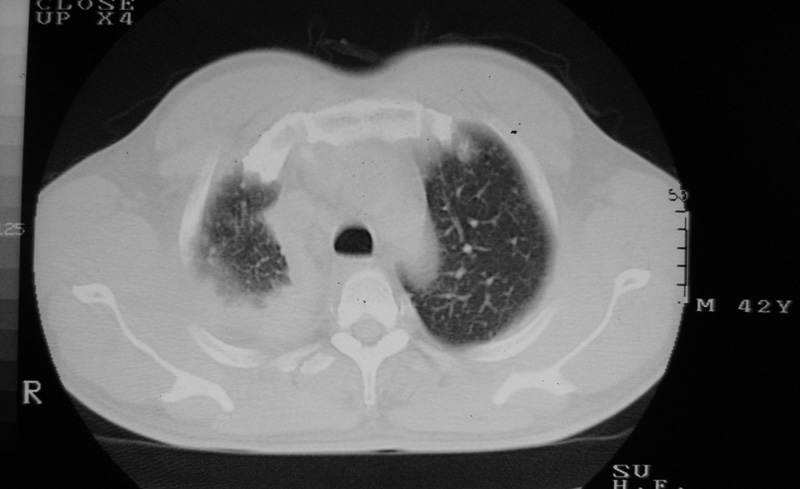

以下是引用守望可可西里在2006-9-11 15:29:00的发言:[br][br] ct平扫表现:右侧胸膜腔缩小,积液,胸膜增厚且不均匀、不规则,以纵隔胸膜增厚为主,边缘呈锯齿状,并见附壁内突之结节状肿块影。右肺含气量减少,纹理聚集,右肺门中下部见数个肿大的淋巴结。纵隔无移位,内未见明显肿大淋巴结,双侧主支气管以及各叶、段支气管比较通畅。。[br] 考虑:右侧胸膜恶性间皮瘤,伴肺门淋巴结转移。